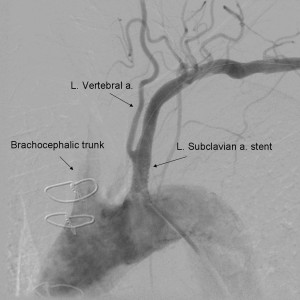

In general, percutaneous intervention with balloon expandable stents has excellent success rates and is of relatively low risk. The procedure is done cannulation of the femoral and/or brachial arteries with a 6-7F sheath. The lesion is crossed with an 0.035 or 0.018 inch guidewire and a balloon expandable stent is deployed in the proximal left subclavian. To minimize risk of distal embolization, some operators use a distal embolic protection device in the ipsilateral vertebral or carotid artery. Restenosis rates are low at 5 years (22%).